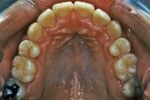

治療後2年経過時